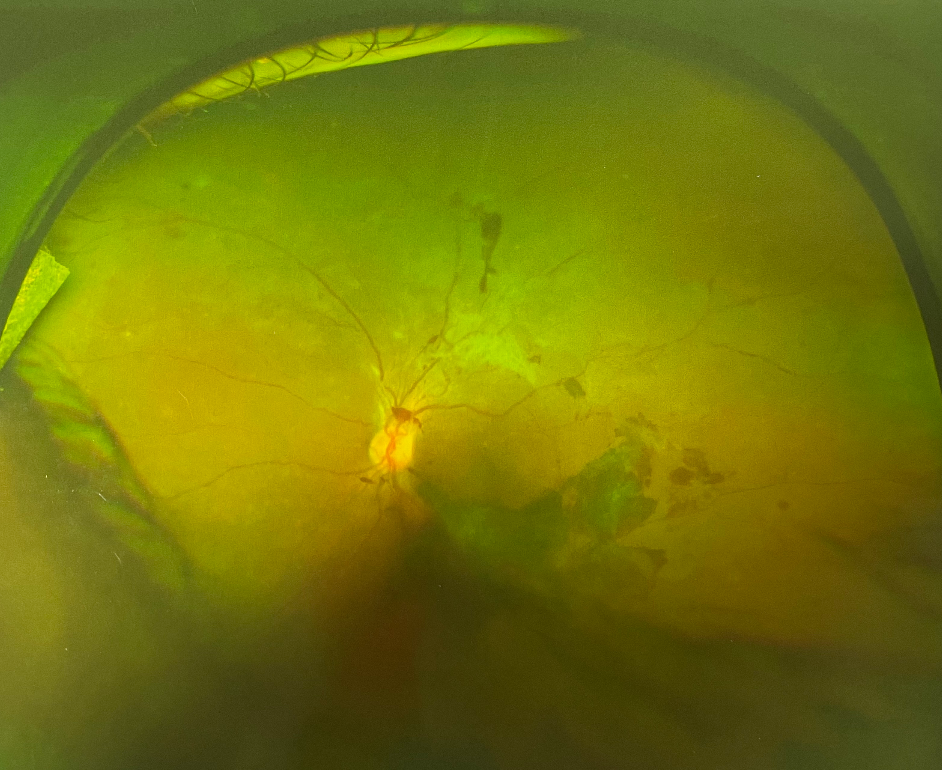

眼底出血并不是一種獨立的眼病,且出血的原因復(fù)雜,對視力的影響也很大。如果不及時加以改善和控制,還有可能引起黃斑病變、青光眼等許多嚴重并發(fā)癥,甚至是失明。很多人沒有出現(xiàn)眼底出血的情況,因而對其不甚了解。那么眼睛眼底出血原因有哪些?今天就和大家一起了解下眼睛眼底出血原因。

老年性黃斑變性引起的眼底出血部位一般限于黃斑變性,好發(fā)于50歲以上的老年人。主要表現(xiàn)為突然視力下降,到了病情晚期,還會出現(xiàn)大面積視網(wǎng)膜下出血、玻璃體出血,對視力的損傷極大

眼睛眼底出血原因2、視網(wǎng)膜靜脈阻塞

如果患者有高血壓、動脈硬化的病史,在出現(xiàn)視網(wǎng)膜靜脈分支堵塞時就有可能出現(xiàn)視力突然下降、視網(wǎng)膜水腫和滲出。若是視網(wǎng)膜指定脈堵塞或視網(wǎng)膜中央靜脈堵塞,患者在眼底出血的同時還可能伴有明顯的視力下降

眼睛眼底出血原因3、糖尿病視網(wǎng)膜病變

當(dāng)糖尿病患者發(fā)生時視網(wǎng)膜病時便會出現(xiàn)眼底出血。在病癥初期,大都表現(xiàn)為少量點狀出血,并伴有微血管瘤。隨著病情的發(fā)展,患者的眼睛可能會有點狀的出血和滲出,有的患者還會有黃斑病變及視力下降的癥狀。因此糖尿病患者一定要按時按量的服用藥物,只有將糖尿病的癥狀控制了才能有效控制眼底出血這一情況。